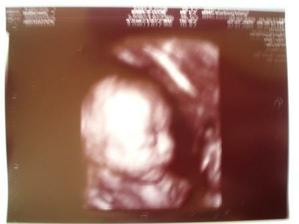

ovulace dorazila v prosinci,ale nic, přišla mrcha , další ovu 26. DC, poté 11 DPO pozitivní test , tj.5.2.09, nádhera